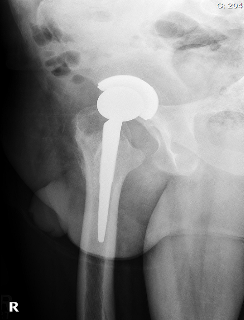

Postoperative radiographs were satisfactory: